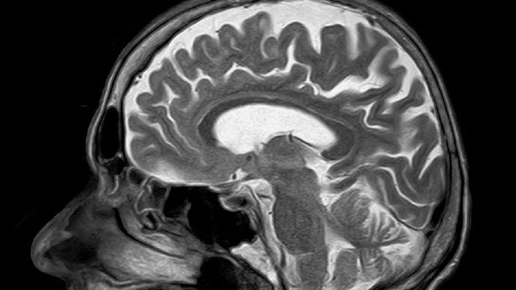

Если все время склонять голову над экраном смартфона, то на затылке вырастет шип

Такие наросты на затылочной кости черепа были впервые обнаружены в 1800-х годах. Но тогда они попадались крайне редко. Теперь же шипы встречаются всё чаще. Мы можем спокойно нащупать костяные шишки пальцами или увидеть их на затылках лысых людей. Шипы эти не маленькие — около трёх сантиметров. У молодых людей они развиваются быстрее. На данный момент они чаще всего встречаются у 18-30-летних. Учёные из университета Саншайн-Кост в Австралии проанализировали данное явление. Они сделали рентгеновские снимки затылков более чем тысячи участников исследования в возрасте от 18 до 86 лет...